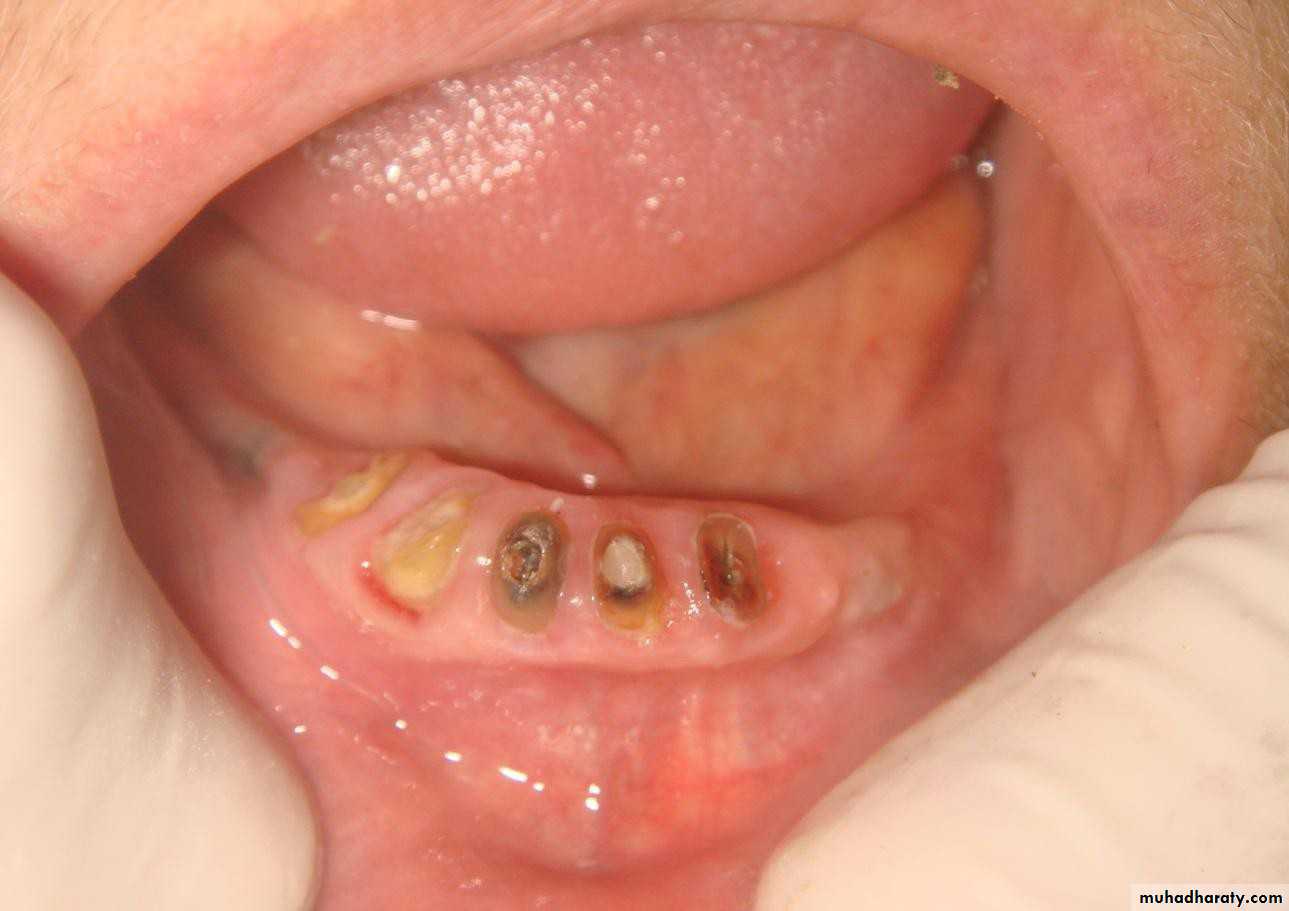

• .Endodontic therapy and amalgam plug

• .Endodontic therapy with post and cast coping• 5- Endodontic therapy with cast